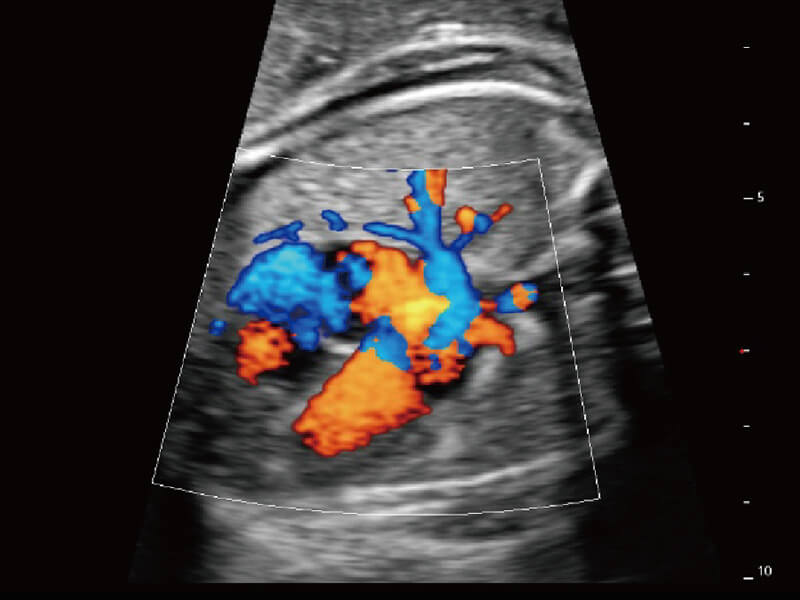

S60创新的探头工艺、高精度模数转换系统、前沿的波束重建技术,从前端信号处理每一个环节采集无损声学数据,真实还原组织原貌,再现解剖细节。

创新的超宽频带技术,为容积成像带来优质的二维图像基础,为您呈现更丰富的结构细节,栩栩如生地展示宝宝的宫内形态以及各种组织的立体结构。